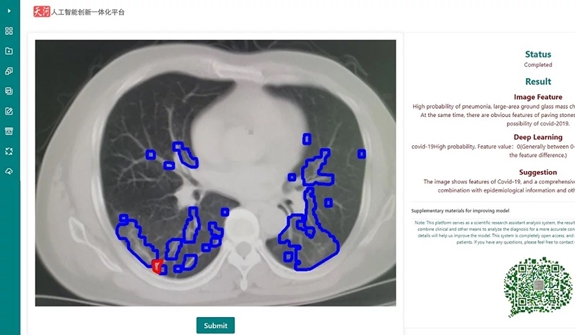

Hệ thống có cài đặt giao diện Tiếng Anh và sử dụng màu sắc để khoanh tròn vùng khả nghi ở phổi của bệnh nhân, giúp bác sĩ dễ dàng nhận biết và chẩn đoán. Tỷ lệ chính xác của máy tính là hơn 80% và đang cải thiện từng ngày.

Ngoài ra, máy tính cũng ước định mức độ nhiễm bệnh của người bệnh theo cấp độ từ 0 đến 10, chỉ số càng thấp thì khả năng mắc bệnh càng cao. Sau đó, nó đưa ra lời khuyên dựa trên kinh nghiệm và kết luận từ các bác sĩ đã từng điều trị cho bệnh nhân nhiễm virus SARS-CoV-2 trước đó.

Giao diện của phần mềm AI phân tích một hình ảnh CT của bệnh nhân Covid-19. |